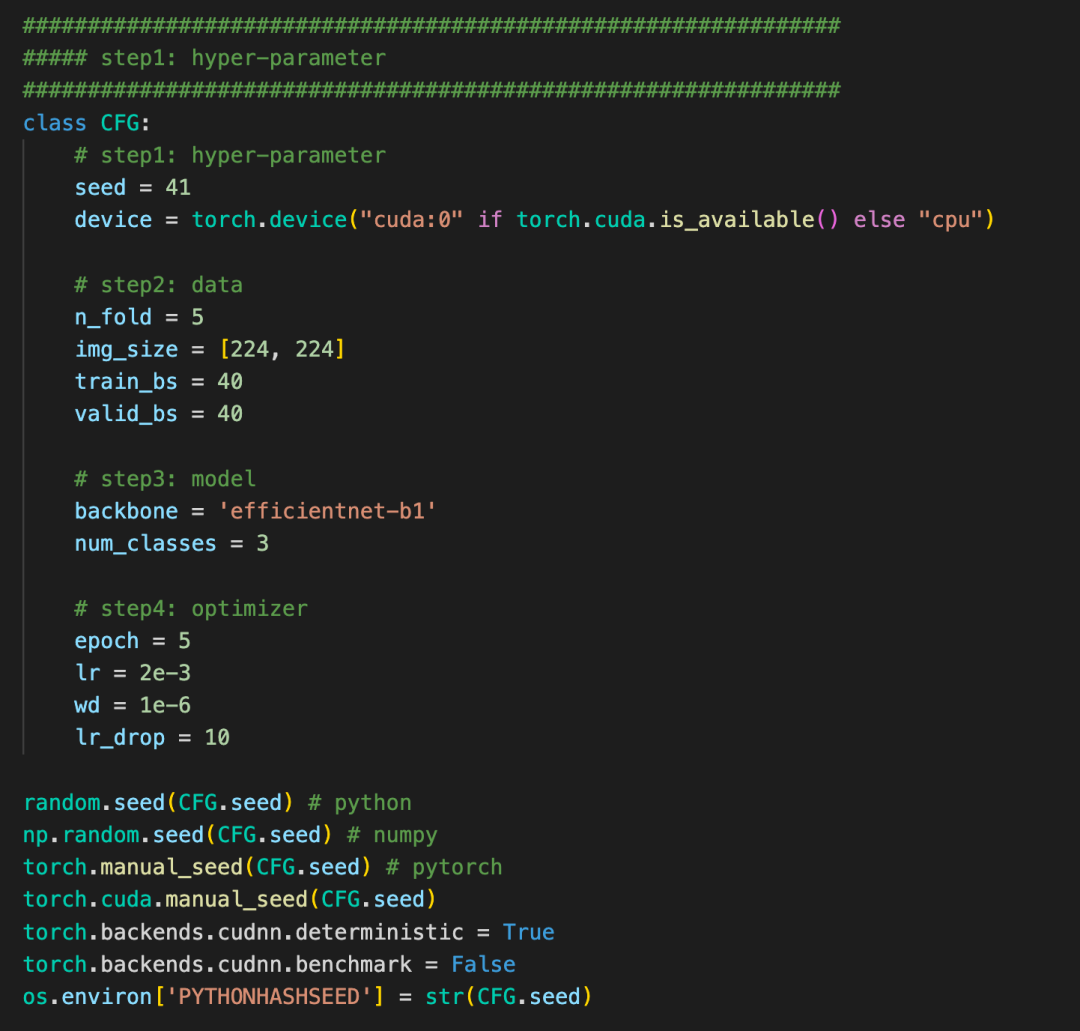

4、baseline

本次提供的baseline分为hypre-parameter, data, model, Loss, train五个方面。

整套baseline的代码非常清晰, 非常适合入门以及后续代码复用。